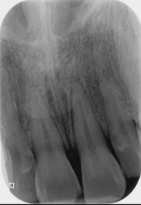

subluxation

tooth is mobile without diplacement

concussed tooth

subluxation of tooth

subluxation follow up

evaluate discoloration, pain and continued motility